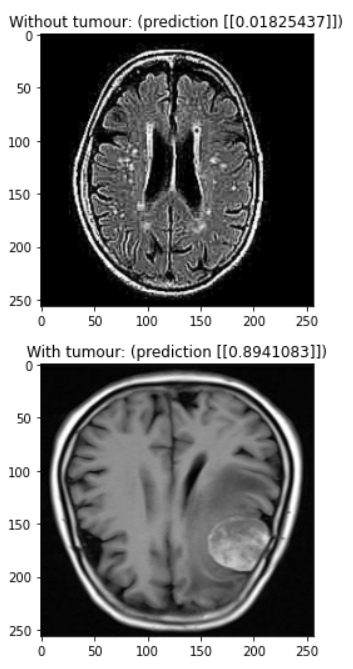

Our model is a convolutional neural network designed to detect brain tumours in MRI scans. You need a trained doctor to conclusively find a brain tumour, but our model can rule out scans that definitely don’t have a tumour and flag potential tumours for evaluation by a human doctor.

We used a combination of batch normalization and dropout to reduce overfitting, allowing us to train for over 80 epochs before noticing any overfitting. The main feature detection layers consist of convolutional layers with batch normalization where every second or third layer has a stride of (2, 2) to downsample the image. Each of these convolutional layers uses the ReLU activation function. We added a dropout of 0.2 in between the final convolutional layer and the output layer to reduce overfitting. We added this while struggling with a problem with our data, so it would be interesting to try removing this layer to see if it’s really necessary. Finally, our output layer is a single dense neuron with a sigmoid activation function. It would be interesting to experiment with using logits instead of a probability output.

Despite our different time zones, we were able to get together to work and accomplish the tasks. Utilizing different skill sets, we were also able to create a high-standard slide presentation and present with the passion that we have for the project. Additionally, after running into some issues, we were able to achieve a diagnostic accuracy of 90% in the time that we had.